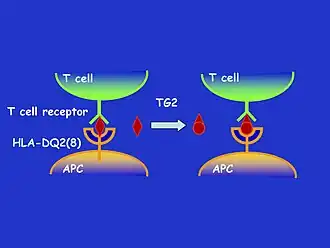

Tissue transglutaminase

Tissue transglutaminase modifies gluten peptides into a form that may stimulate the immune system more effectively.[43] These peptides are modified by tTG in two ways, deamidation or transamidation.[44]

Deamidation is the reaction by which a glutamate residue is formed by cleavage of the epsilon-amino group of a glutamine side chain.[45] Transamidation is the cross-linking of a glutamine residue from the gliadin peptide to a lysine residue of tTg in a reaction that is catalysed by the transglutaminase.[44] Crosslinking may occur either within or outside the active site of the enzyme. The latter case yields a permanently covalently linked complex between the gliadin and the tTg. This results in the formation of new epitopes believed to trigger the primary immune response by which the autoantibodies against tTg develop.[46]

There are seven HLA-DQ variants (DQ2 and DQ4–DQ9). Over 95% of people with coeliac disease have the isoform of DQ2 or DQ8, which is inherited in families. The reason these genes produce an increase in the risk of coeliac disease is that the receptors formed by these genes bind to gliadin peptides more tightly than other forms of the antigen-presenting receptor. Therefore, these forms of the receptor are more likely to activate T lymphocytes and initiate the autoimmune process.[36]